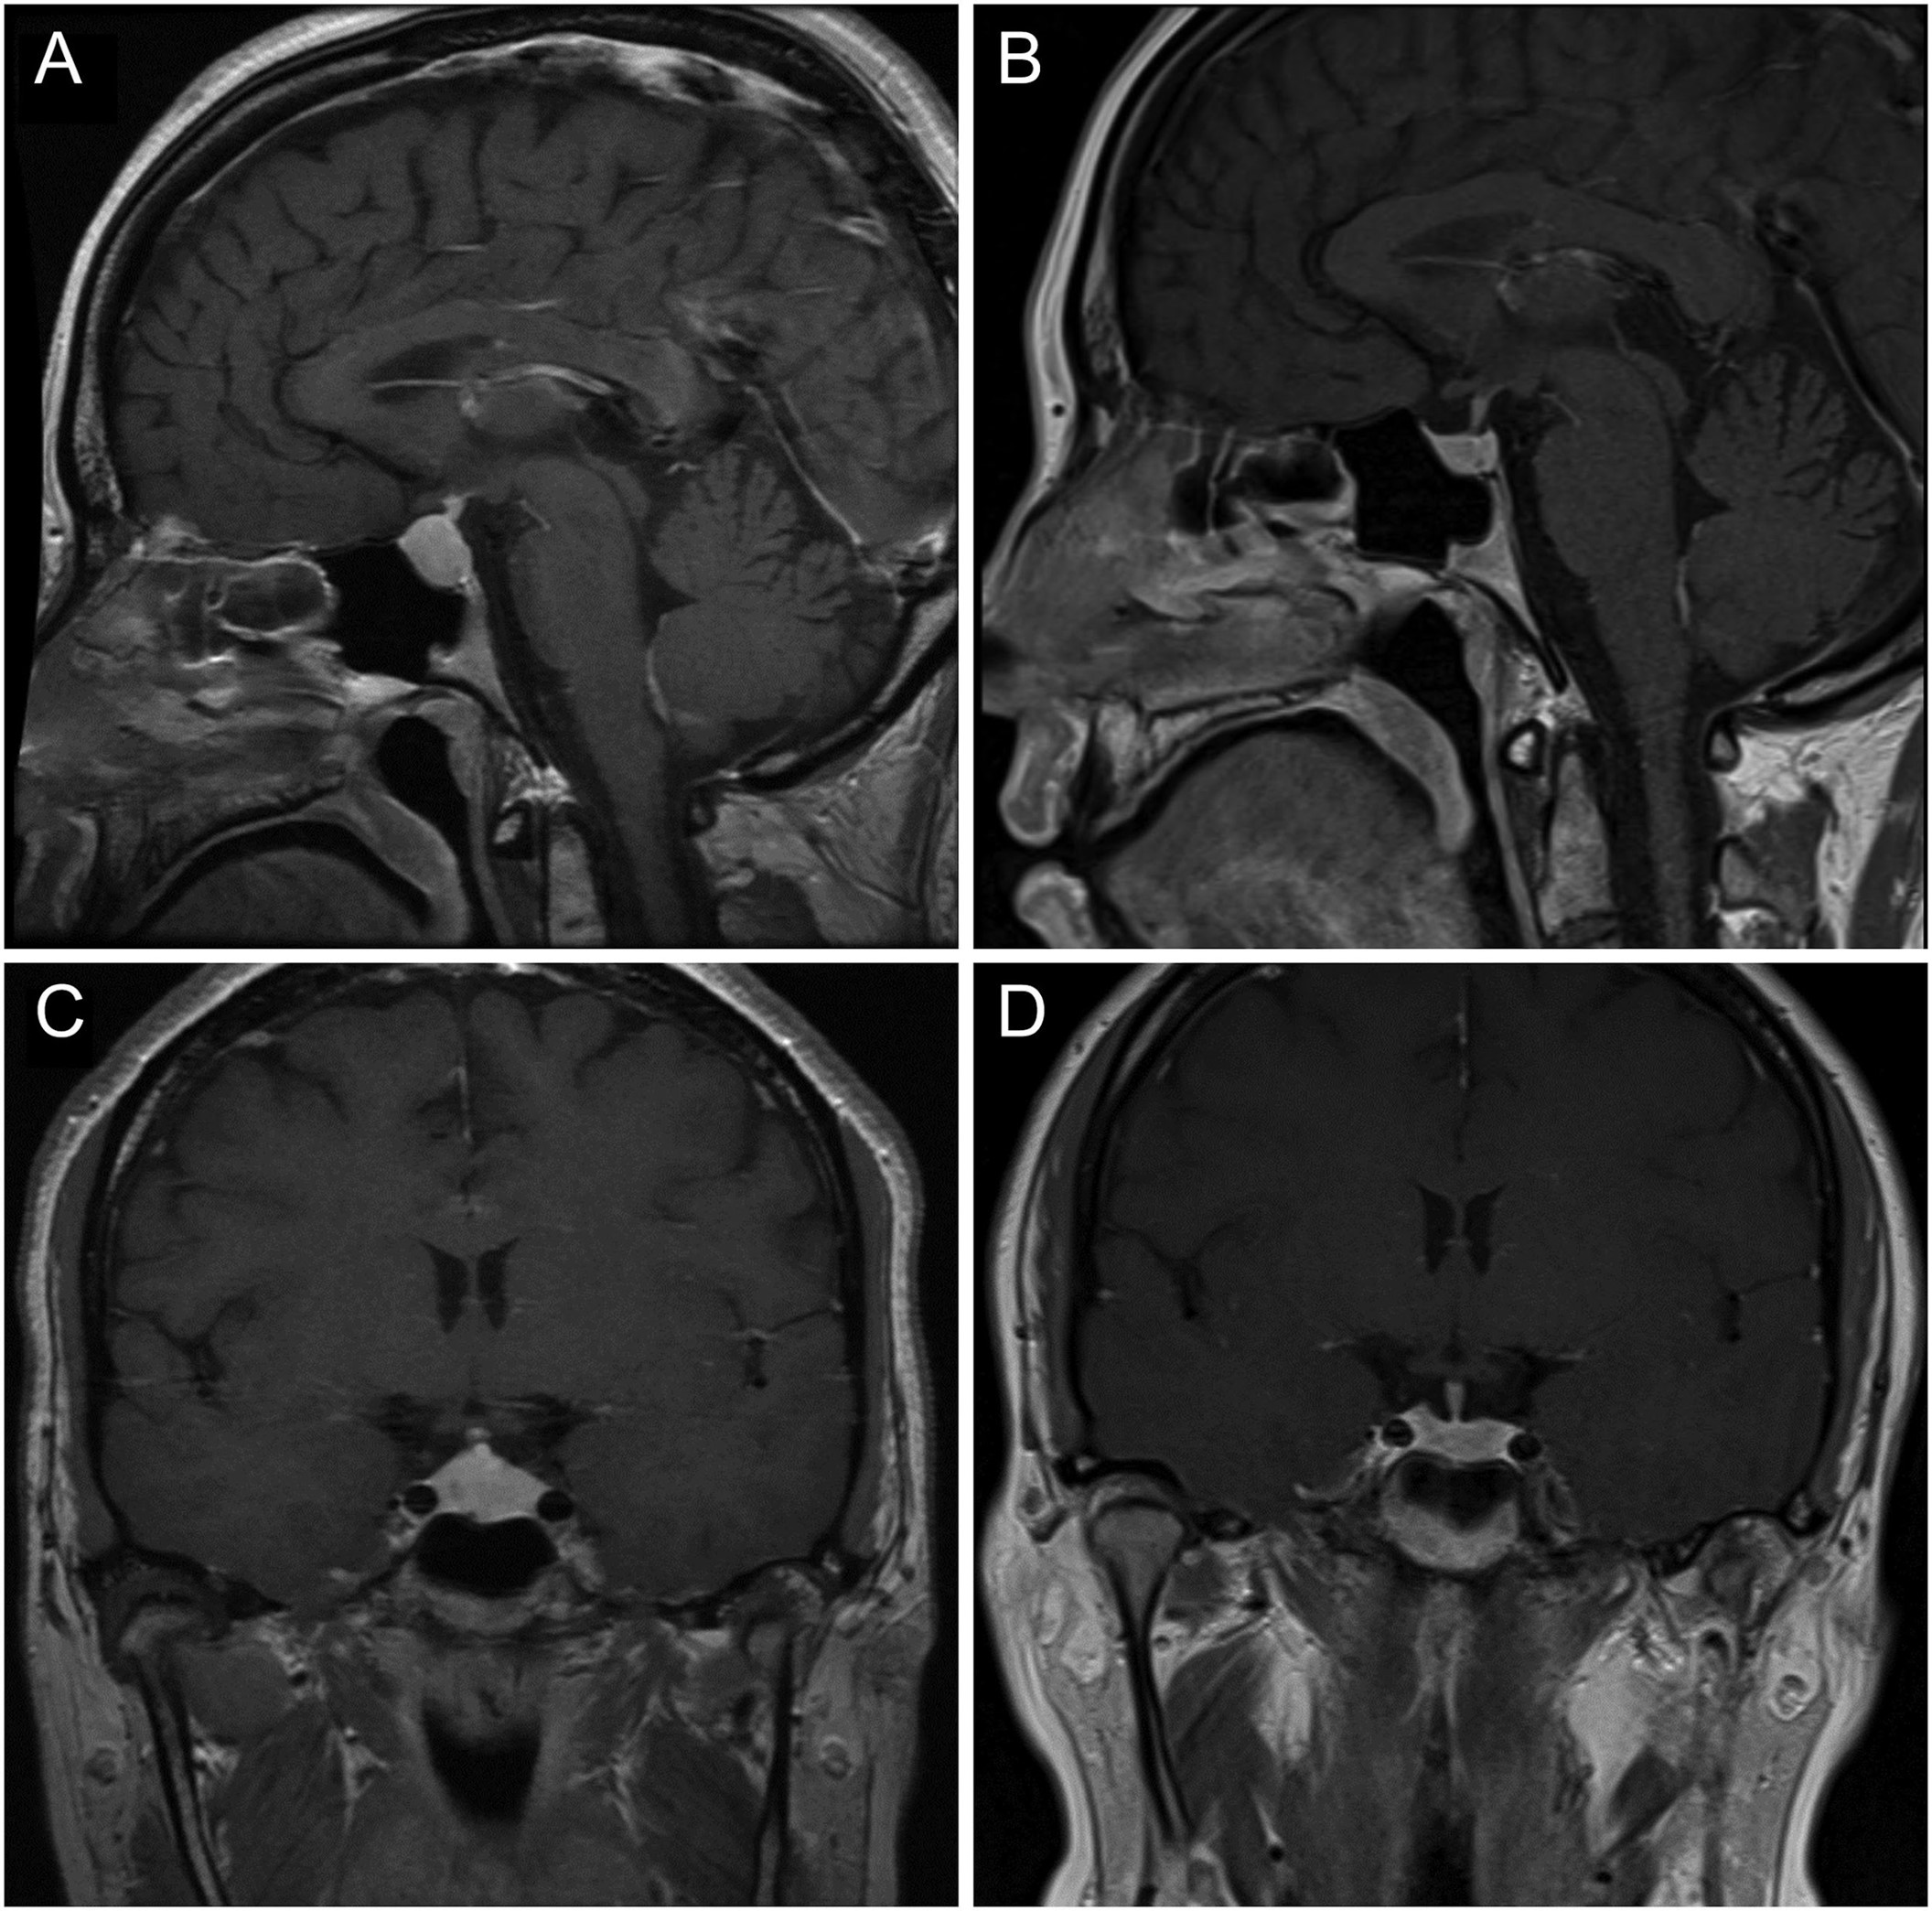

MRI 垂体显示明显增生,延伸至鞍上方,但没有影响视神经交叉系统,垂体高度为 13 mm(图 1A和C)。

图1:2013 年 10 月(A 和 C)和 2017 年 6 月(B 和 D)的垂体窝横切和矢状切面的 T1 加权 MRI 图像(对比后)。在恢复一致的甲状腺素替代后,垂体大小明显减小。

2017 年 6 月重复进行垂体 MRI 成像,结果显示垂体大小正常(图 1B和D)。血液结果还显示催乳素正常化至 140 mIU/L(参考范围:110–560 mIU/L)。